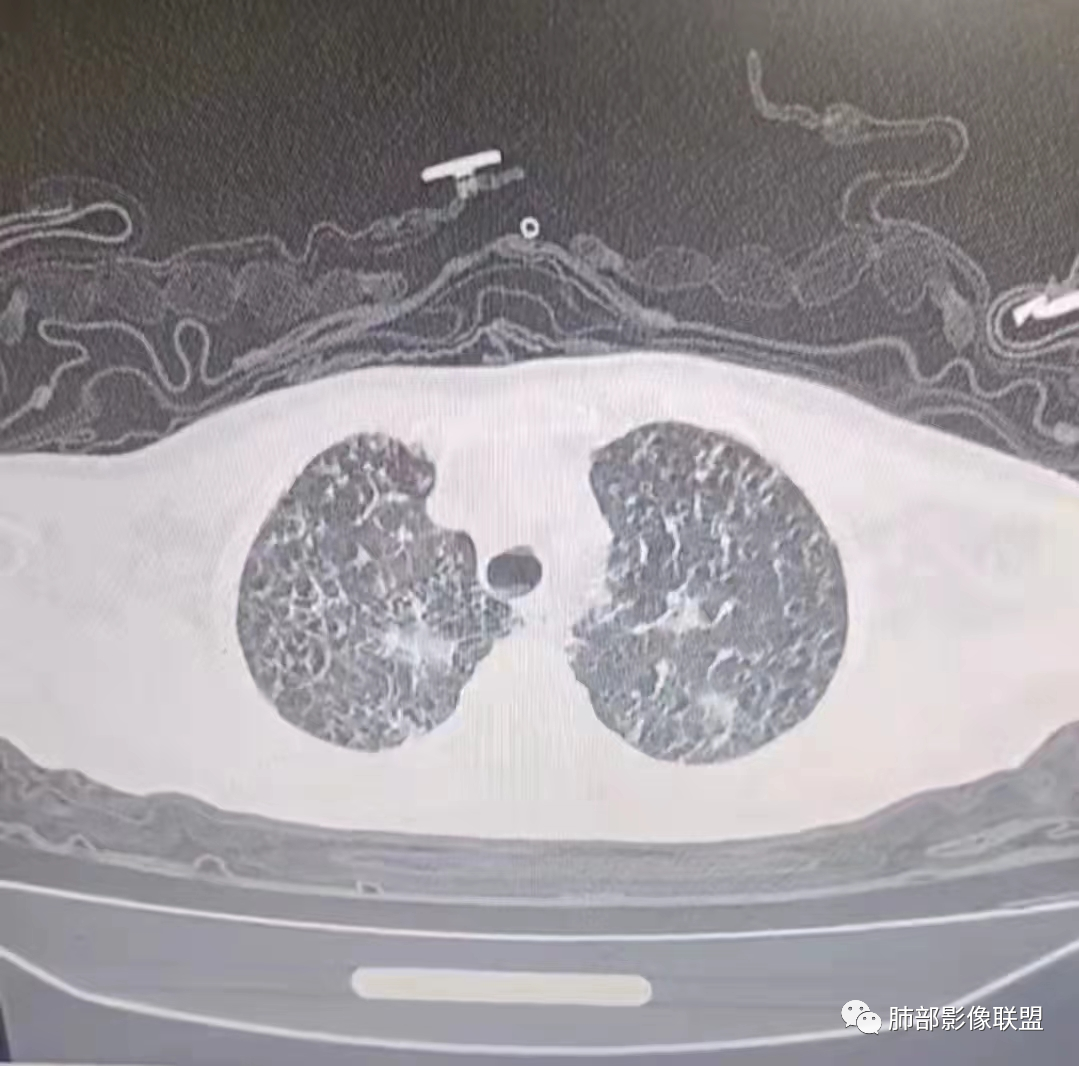

2、影像特点:右肺中叶、左肺下舌段可见支扩。左肺下舌段及两肺下叶可见片状实变影及发结节影,病灶边界多显示不清,纵隔窗显示病灶密度较均匀,未见液化、空洞或钙化。左肺下叶部分病灶沿支气管分布,并可见局部支气管管壁增厚。

2)病灶密度较均匀柔和,边界不清,没有树芽征,没有新旧不等,病情反复,吸收变化较快,显然不符合结核或非结核分枝杆菌感染。

多发腺泡结节,部分融合小叶实变。